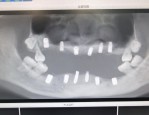

湖南岳阳32岁女子全口仅剩4颗牙,侵袭性牙周炎导致严重口腔问题

湖南岳阳32岁的朱女士虽然年纪轻轻,全口却只剩下了4颗牙,不仅没法正常吃饭,颜值也受到了影响。 从22岁起,朱女士就发现自己的牙齿逐渐松动,甚至脱落。最开始她以为只...